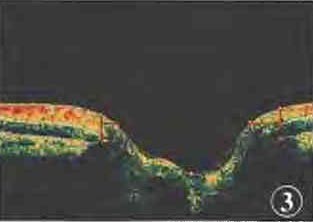

Optovue频域光学相干断层扫描(optical coherence tomography,OCT)检查:

盘缘面积右眼1.81mm2、左眼1.13mm2,

杯盘面积比右眼0.23、左眼0.51,

神经纤维层厚度上半侧右眼112.53mm、左眼95.99 mm2(图3)。

图3:左眼视盘OCT 视盘凹陷扩大、加深